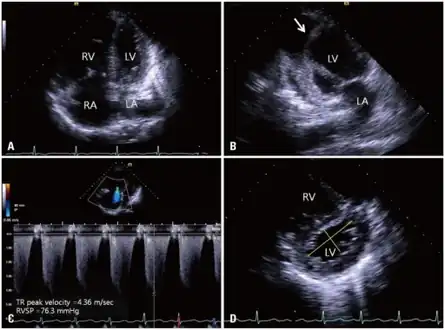

a-d)2DE (two dimensional echocardiography) features of cor pulmonale -

Normal heart (left) and right ventricular hypertrophy -